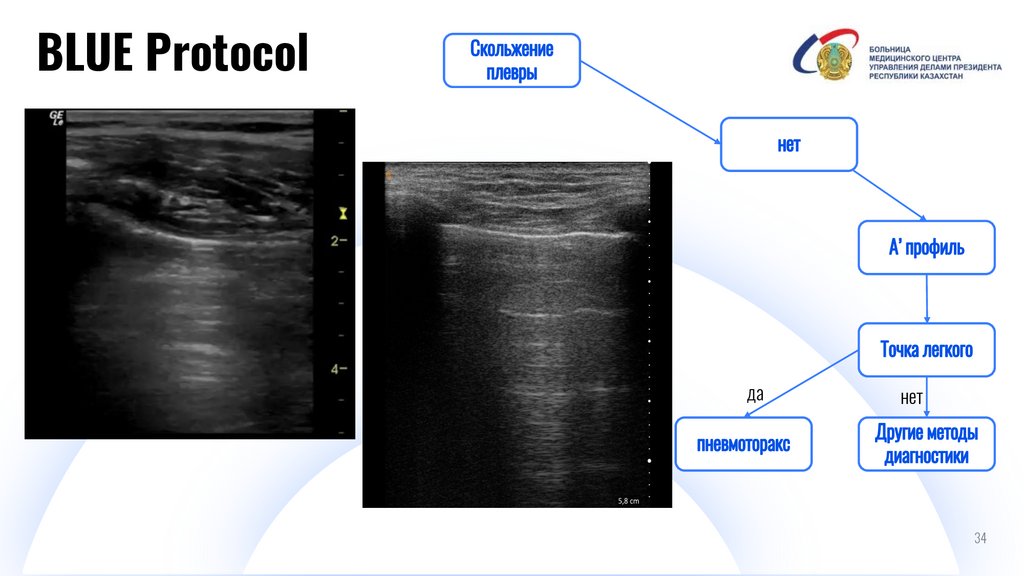

BLUE Protocol

И

Digital IT pitch-deck PowerPoint bundle

да

нет

34